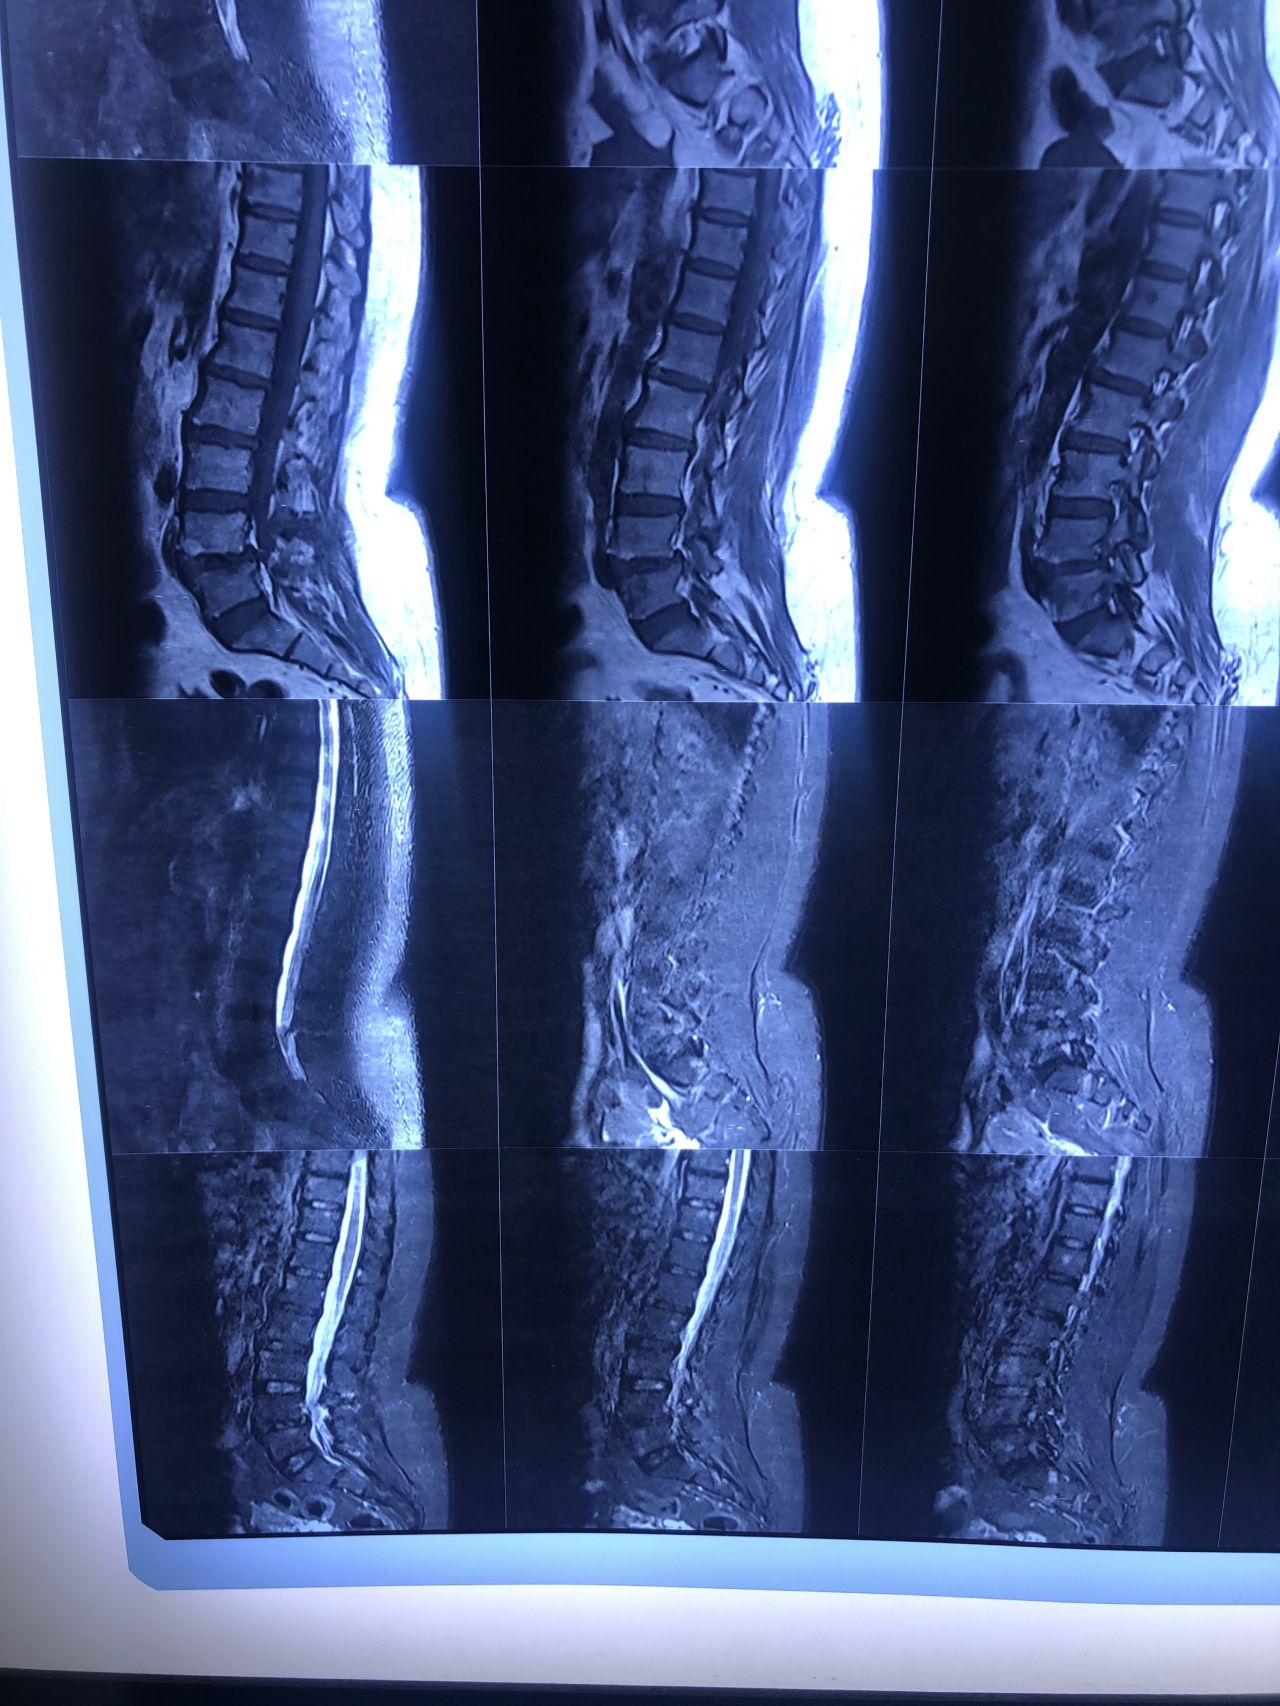

40 yrs old male patient presented to my office who had severe R gluteal pain and radicular pain along R L5-S1 now pain has reduced by 80% in his motor exam had R big toe L5 motor reduced to 4+\5 and R S1 DTR was 0 while L S1DTR was 1+

We did EMG/NCV which showed Mod- sever R L5 S1 irritation without any active axonal loss

I had to decide to refer him for surgery or not patient didn’t have any treatment meanwhile

I ordered new L/S mri

I posted his new mri and old mr

Which was 20 days ago and have posted all below

The first 12 mris had been done 20 days ago

After those first 12 MRIs i have posted new MRIs which were done yesterday

After seeing his new mri and emg/ncv and getting sure his neurological deficit is not active and progressing i told patient he doesn’t need surgery at this time and released him with some advices and exercises

Keep in mind when patient is 80-90 percent pain free and stable i would never give treatment to them just give exercises and follow up their condition